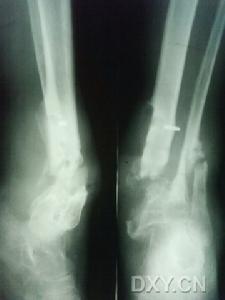

此後,在假關節脛骨內側準備好植骨創面修整成平面,最大限度地使植入骨板與脛骨緊密相接植骨儘量多放於遠側端但不可損傷骨骺板整個骨板越長越好,為保持長度健康搜尋,脛骨上、下端可有少許空隙腓骨根據脛骨病變切除長度可切除一部分或火罐網不切除,保持完整腓骨能增加脛骨的穩定性火罐網。然後,上下端各用2枚螺釘固定脛骨植入骨板健康搜尋,火罐網在移植健康搜尋的骨板中間或脛骨上下端空隙中植入多量的骨松質(圖1)。縫合皮下組織及皮膚鵻為保持局部血運不要縫合深筋膜。術後用長腿石膏固定火罐網對於肥胖患兒可用單髖人字石膏固定鵻10~14天拆線,再更換石膏固定4~6個月。拆除石膏後仍套用長腿支架火罐網直至骨骼成熟雖有骨性連線但易產生再骨折,因此外固定甚為重要